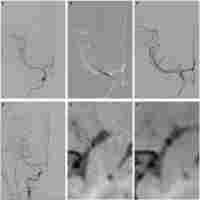

| Abstract | Symptomatic intracranial atherosclerotic disease (sICAD) remains a challenging disorder in the neurovascular field. Despite best medical treatment (BMT), the recurrence rate for stroke remains high in patients with intracranial high-grade stenosis (>70-99%). Furthermore, two large randomized trials (SAMMPRIS and VISSIT) failed to prove the efficacy of percutaneous transluminal angioplasty and stenting (PTAS) in patients with sICAD. Drug-coated balloon percutaneous transluminal angioplasty (DCB-PTA) represents an alternative treatment modality with therapeutic benefits for interventional cardiology. However, there are very few articles in the existing literature that relate to the use of DCB-PTA in sICAD patients. Here, we aimed to review the rationale underlying the use of DCB-PTA in sICAD patients and summarize recent developments in the neurovascular field. |